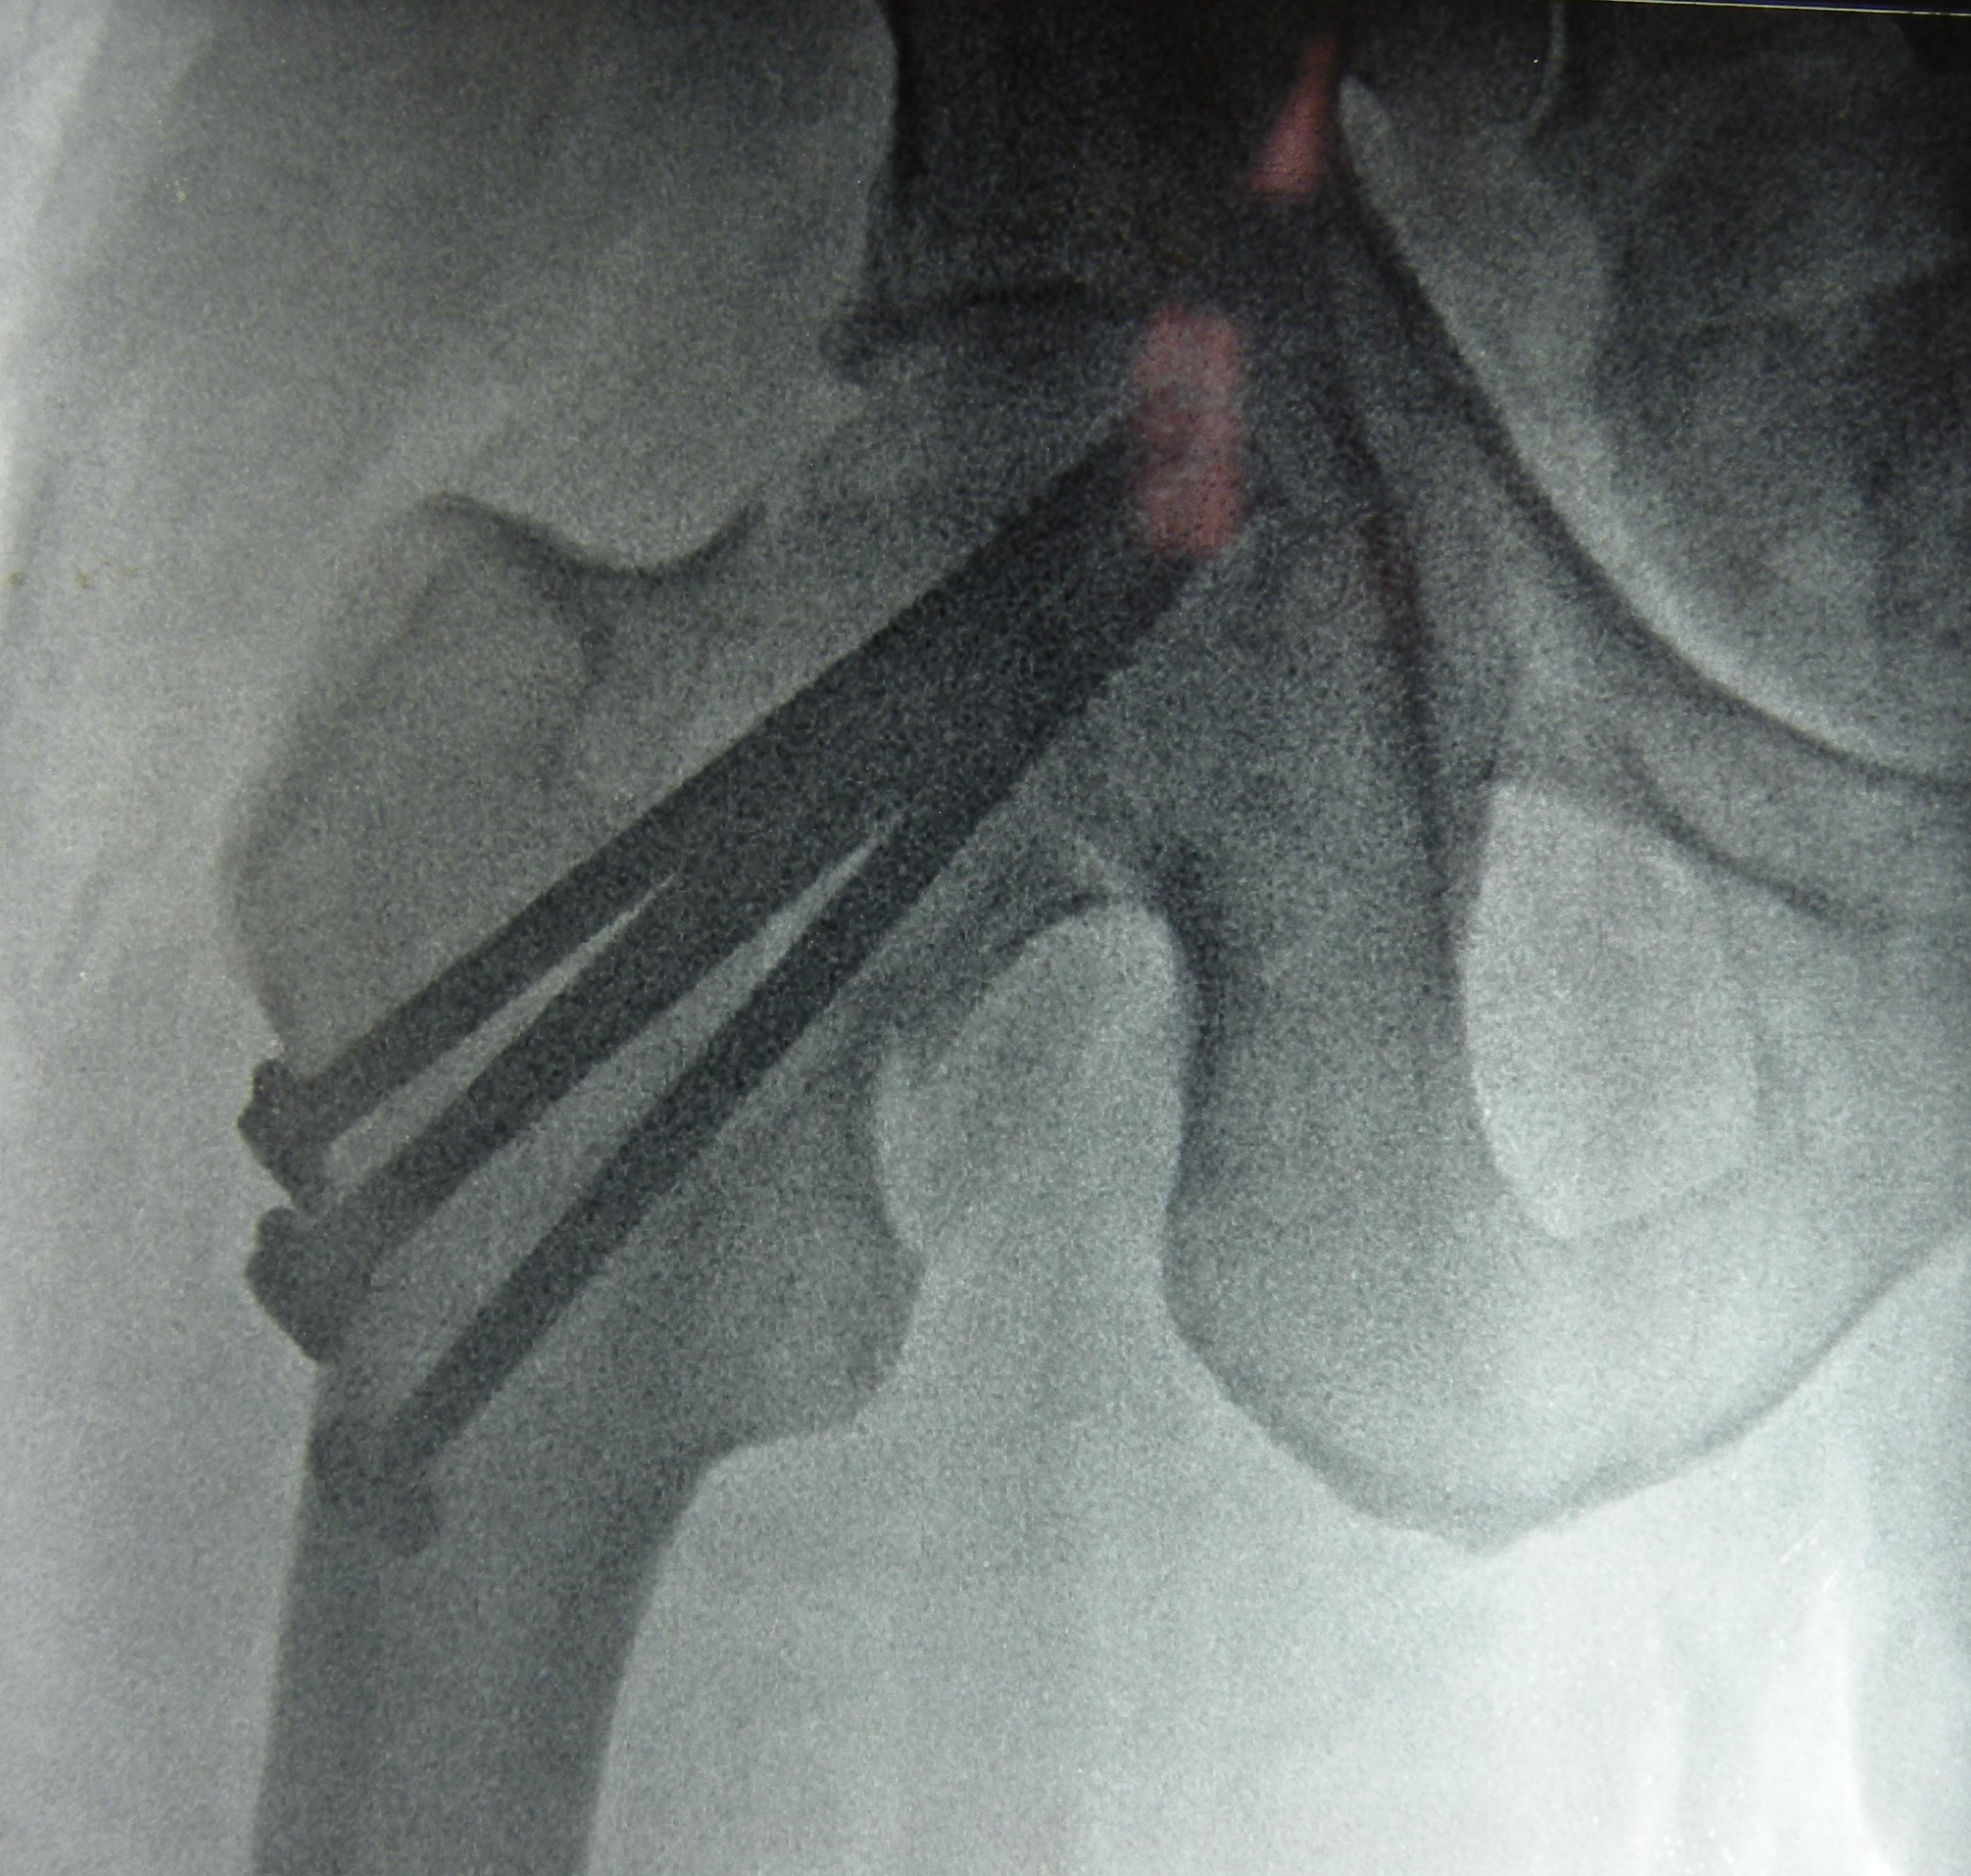

my-fracture-2-postop-b